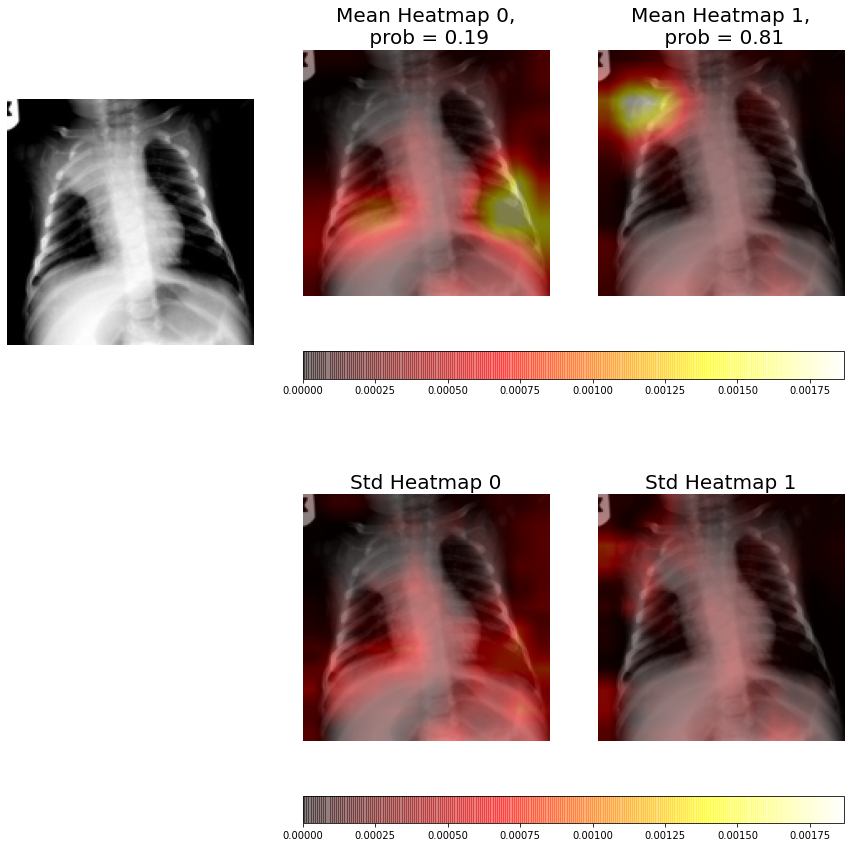

The ensembles are composed by five individual CNNs, therefore, for each radiography we have five different heatmaps for each class (consolidation / non-consolidation). This allows us to compute the average heatmap and the uncertainty at each pixel (standard deviation at each pixel) for each class.

In Figures 9-11 we can see from left to right, and from top to bottom, the original X-ray, the average heatmap for the "non-consolidation" class, the average heatmap for the "consolidation" class, and the standard deviation heatmaps.

This visual representation provides to medical staff with relevant information. Firstly, the probabilities of each class predicted by the model are shown in the title of each average heatmap. Secondly, the average heatmaps show the areas of the X-rays that are most informative according to the ensemble. Finally, the standard deviation heatmaps provide information about the areas of greatest disagreement among individual CNNs (that is, the areas with the greatest uncertainty). This suggests that medical staff should pay more attention to areas with higher values in the average heatmaps and in the standard deviation heatmaps.

In Figure 10 we can see how the average heatmaps of both neurons have lighted up, whereas only neuron 1 heatmap should light up because signs of consolidation appears in the upper area of the left lung. We can see how the standard deviation heatmap of neuron 0 presents higher values than neuron 1, which means that results of neuron 1 (consolidation class) are more robust than those of neuron 0 (non-consolidation class). If we look at the consolidation class average heatmap, the marked area corresponds to the pathology signs and it also marks a larger area than the same heatmap of the individual CNN (Figure 7). Furthermore, if we look at the estimated probability of the models (81%) and we compare it with the one obtained with the individual CNN (26.7%), we can see that ensembles give greater robustness to the system and avoid possible misclassifications obtained with the stand alone models. obtained with the stand alone models.